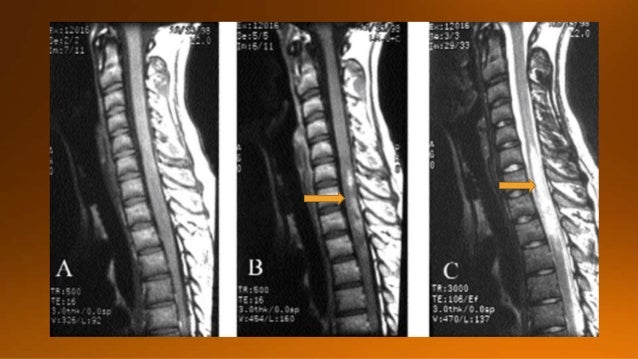

22. 22. These are images of a teenage child with a typical history of respiratory tract infectionThere is swelling and cord involvement and no enhancement The imaging findings and clinical history is typical of ADEM

24. 24. The follow up MR shows that the cord has returned to normal again

25. 25. Another case of ADEM. Notice the typical involvement of the pons and basal ganglia.

26. 26. On follow up scan almost complete normalisation.